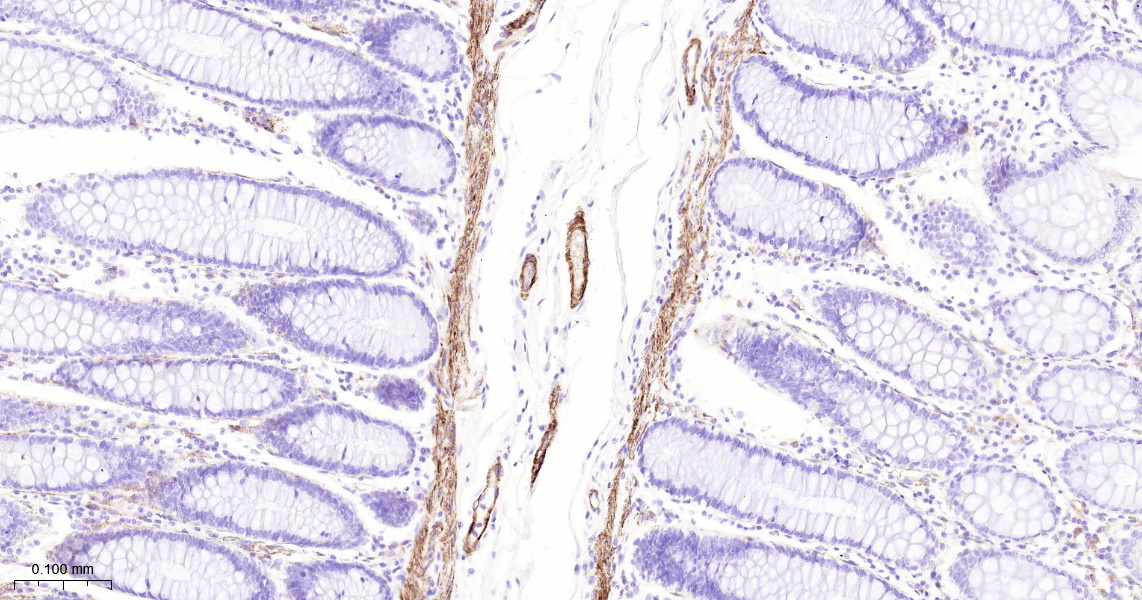

MYL9 Recombinant Antibody

• IHC-P

IHC-P IHC-P1:50-200